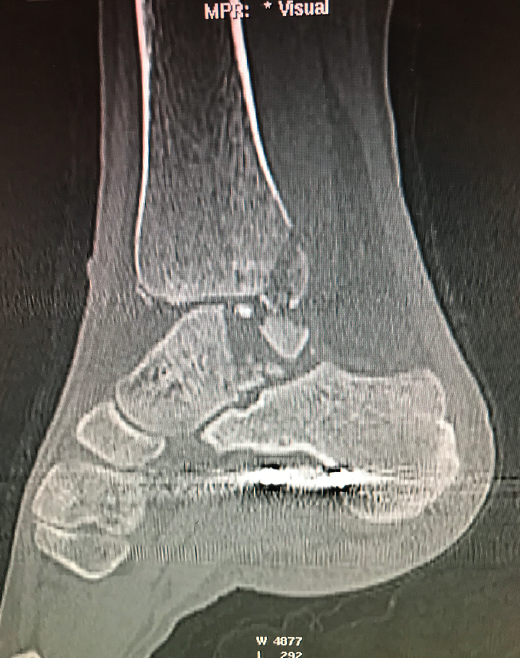

Se trata de un caso del Dr. Cuervas-Mons, publicado en Techniques in Orthopedics(15), acerca de un paciente varón de 54 años que acude a la consulta con dolor del retropié y deformidad en varo. Tras la valoración, se evidencia pseudoartrosis sintomática (Figura 9), por lo que se decide llevar a cabo tratamiento quirúrgico.

- Obtención de las imágenes (Figura 10).